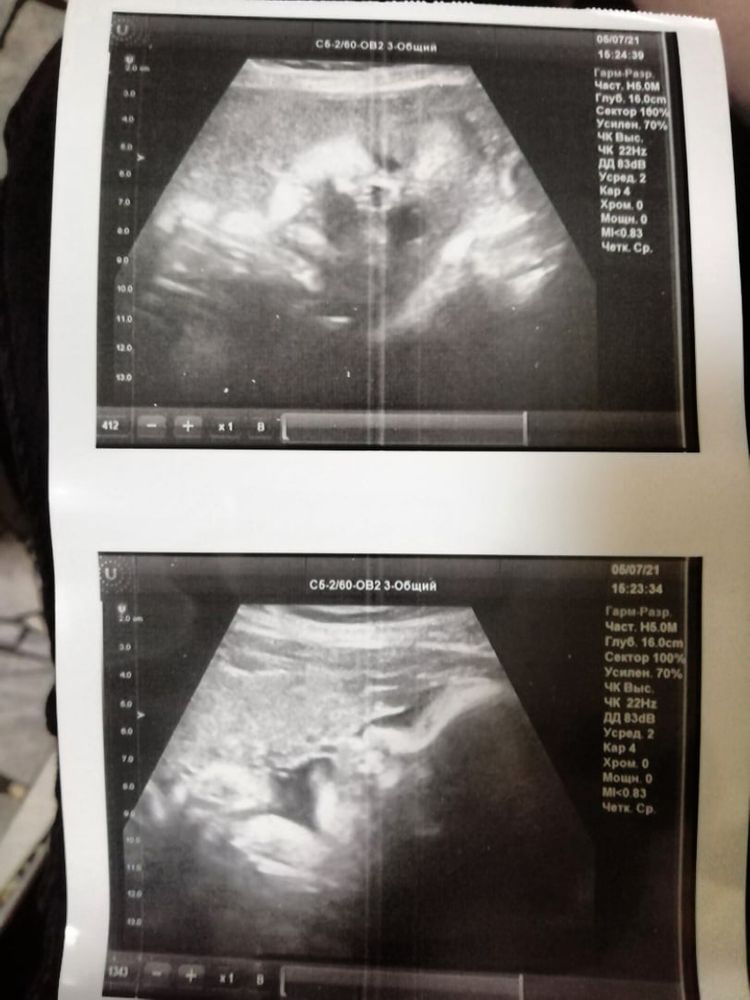

Наш III скрининг ❤️ фото. Самочувствие.

По узи всё замечательно. Лежит головой вниз. Сказали крупненькая девчушка ожидается 🤪